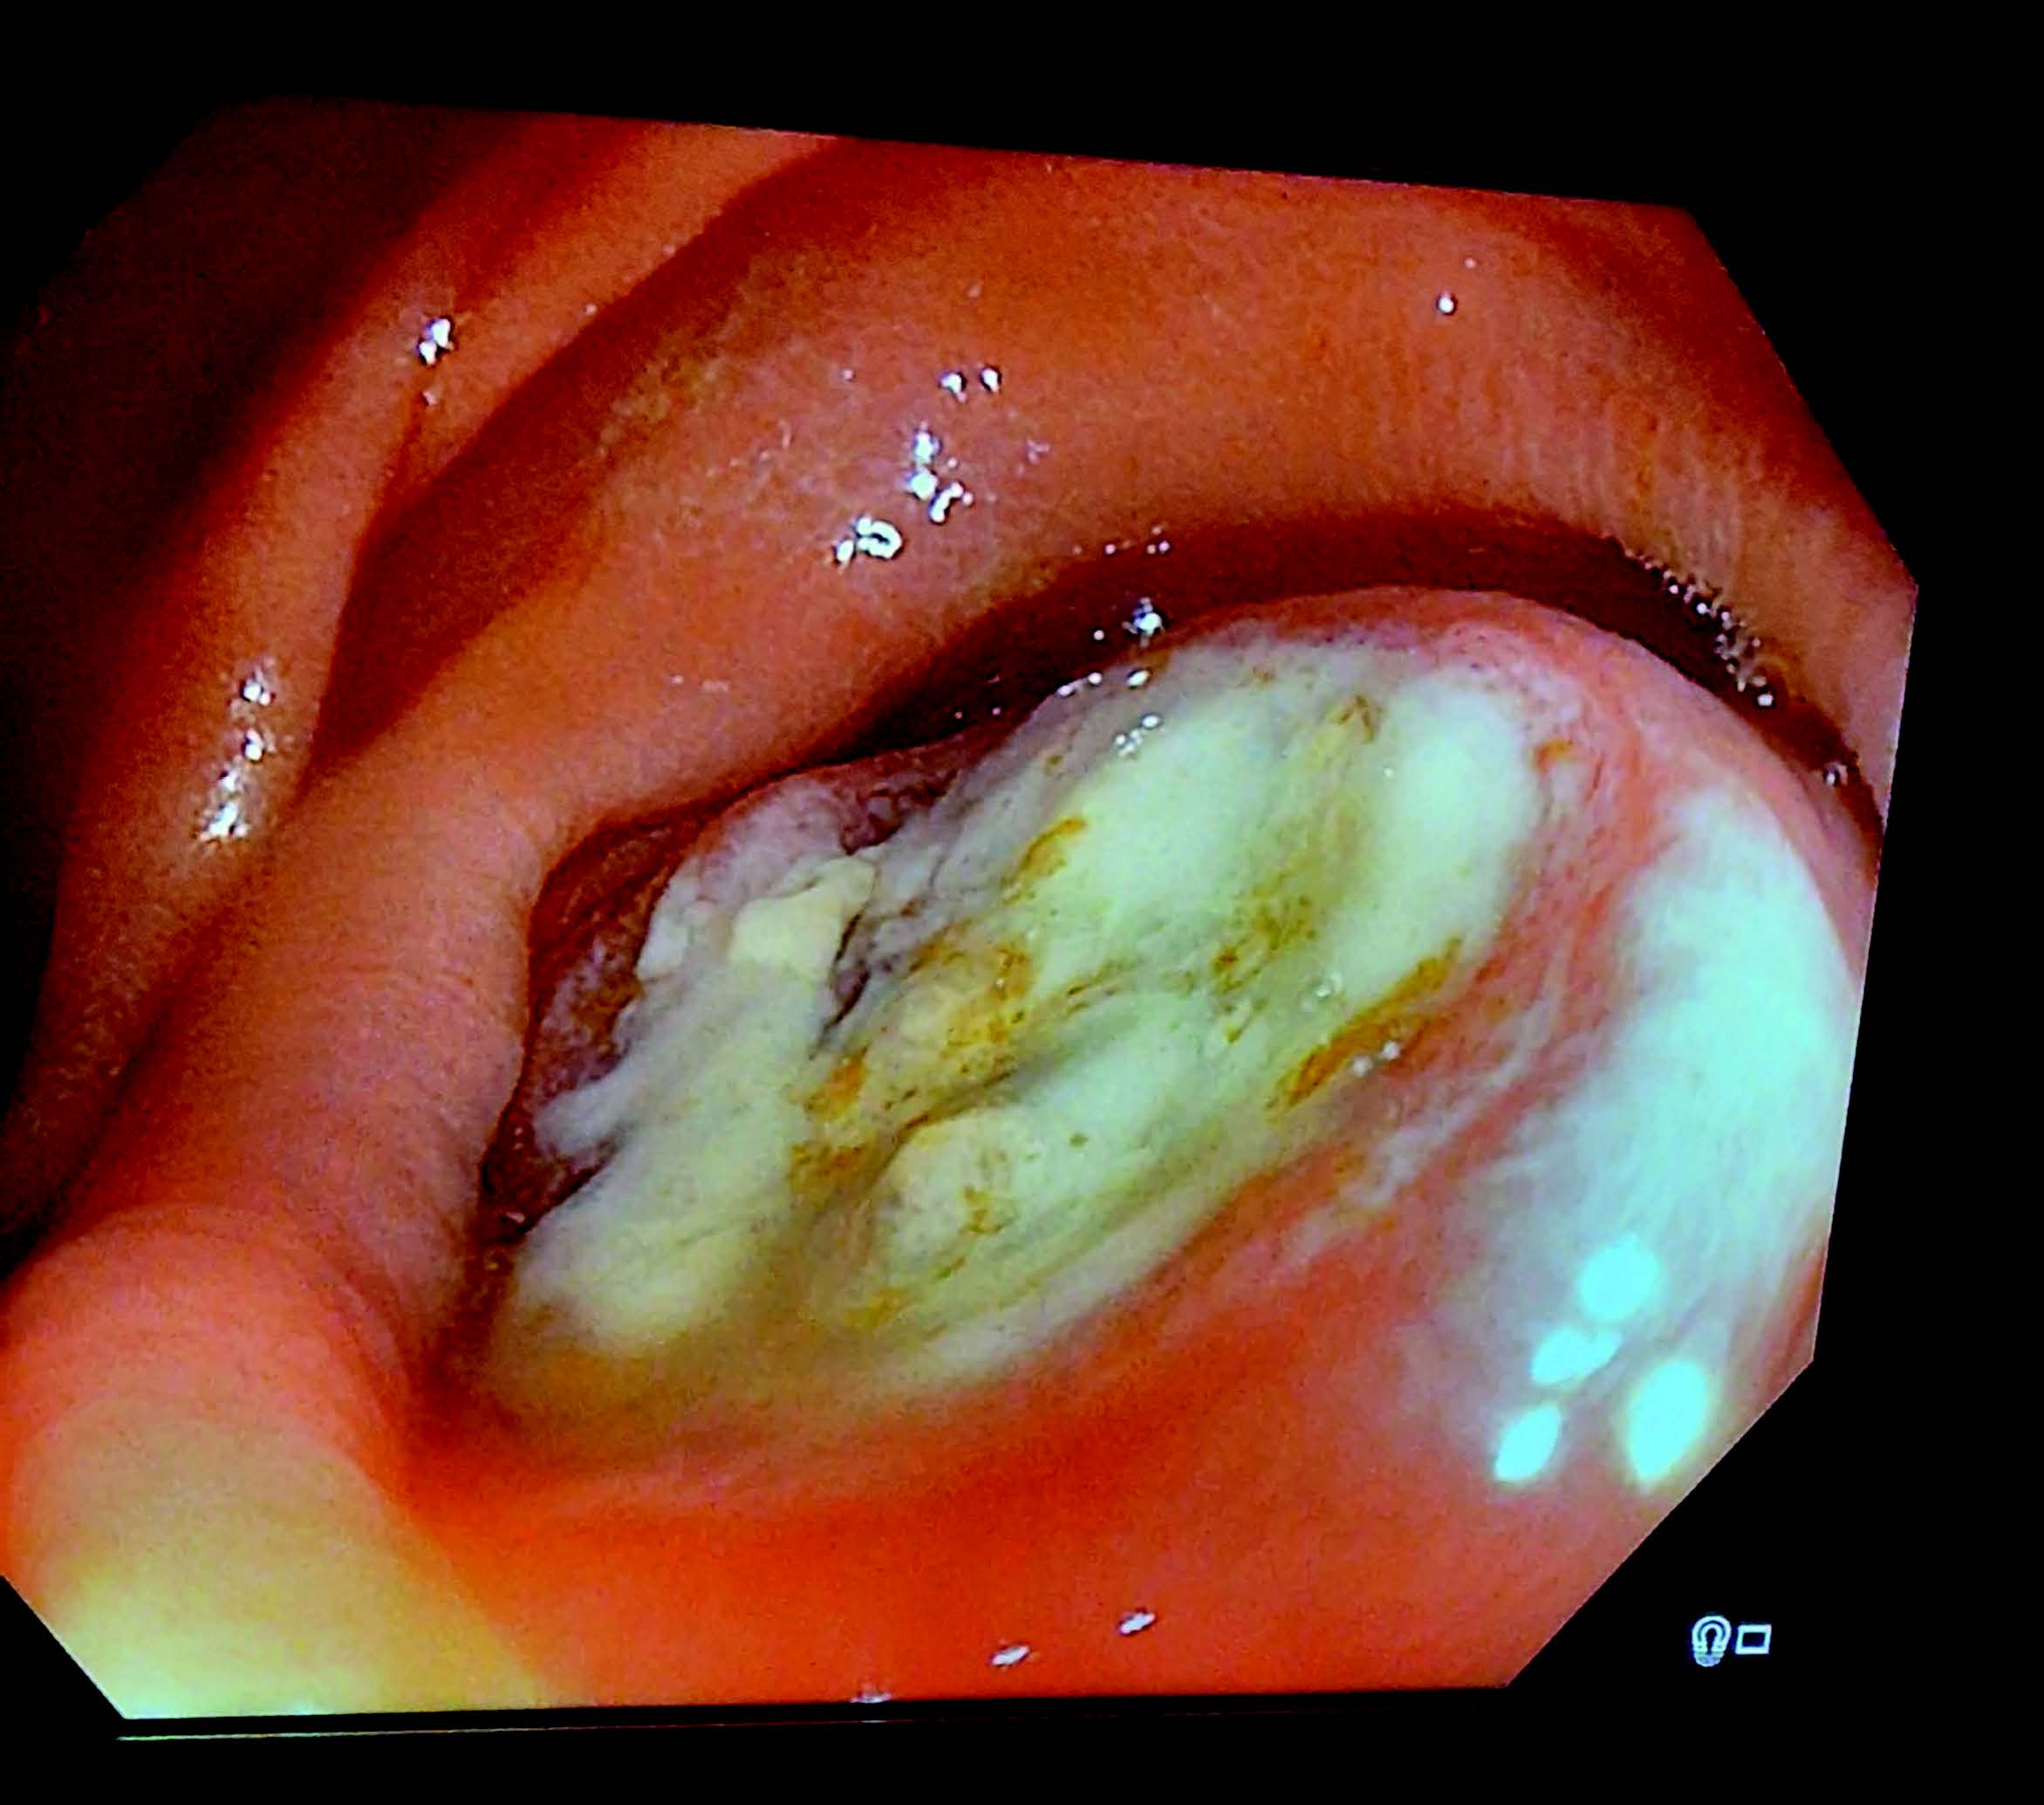

Bildequiz